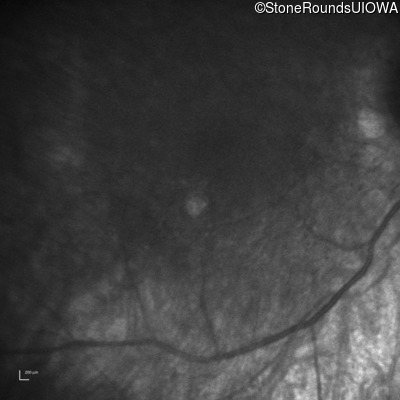

Infrared Fundus Photograph - Right -

No Light Perception

Exemplar

Infrared Fundus Photograph - Left -

Light Perception